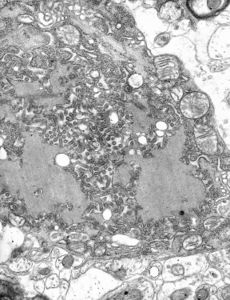

الفيروس له شكل الطلقة، وطوله حوالي 180 نانومتر، وقطر مقطعه حوالي 75 نانومتر.

TEM micrograph with numerous rabies virions (small, dark grey, rodlike particles) and Negri bodies (the larger pathognomonic cellular inclusions of rabies infection).